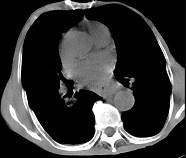

问题 女,71岁,进食时有梗阻感,进行性加重半年,影像检查如图,最可能的诊断是 ( )

选项 A.贲门失弛缓症 B.食管癌并纵隔淋巴结转移 C.食管良性狭窄 D.反流性食管炎 E.食管静脉曲张

答案 B